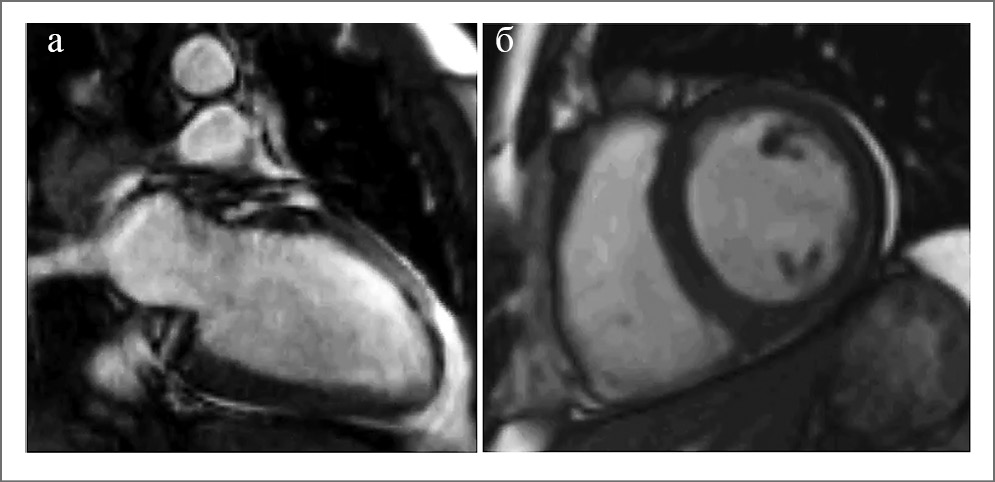

Изображения Т2-ВИ – импульсная последовательность, позволяющая визуализировать отек ткани любой этиологии. Миокард в зоне острого ишемического повреждения на Т2-ВИ выглядит ярким по сравнению с неповрежденным миокардом за счет повышения интенсивности сигнала (ИС) в зоне отека (рис. 3).

Рис. 3. Отек миокарда на Т2-взвешенных изображениях: а – 2-камерная длинная ось ЛЖ, б – 2-камерная короткая ось ЛЖ